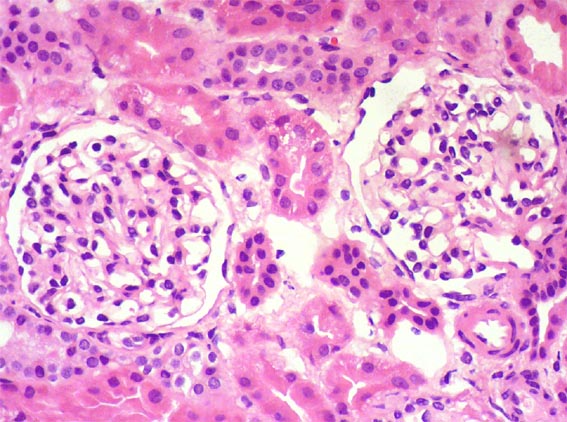

The patient is a 4-year-old girl who presented nephrotic syndrome in the first year of life, with biopsy in which focal segmental glomerulosclerosis was diagnosed. There was no response to multiple treatments. Molecular studies were unable to detect a specific genetic alteration. He developed ESRD at 3 years of age. She was in hemodialysis few months and was transplanted from a dead donor. Nephrectomy of a native kidney was done. Before the transplant, on dialysis, she had low urine output and non-nephrotic proteinuria without hypoalbuminemia or dyslipidemia. After transplantation presented progressive increase in proteinuria. Four post-transplant weeks there was complete nephrotic syndrome with proteinuria >100 mg/m2/h, dyslipidemia and hypoalbuminemia. Serum creatinine 0.5 mg/dL.

A renal biopsy was done, see the images.

Figure 2. H&E, X200.